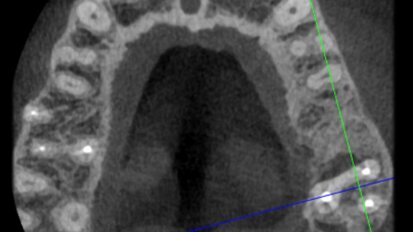

Motivated by his desire to simplify the treatment process for patients, Dr Philip Tan has developed a full-arch implant-retained prosthesis for completely ...

Treatment of edentulism with Pro Arch BLX focus of free webinar

LONDON, UK: When it comes to implants, the Straumann Group has been one of the major dental brands leading the way. In a free upcoming Straumann Group ...